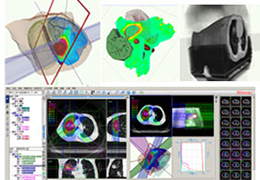

Data Analysis

Data Analysis

Data analysis includes preprocessing, correlation analysis, determination of Talairach coordinates, volume rendering, surface rendering and cortex flattening.

Preprocessing includes motion correction, Gaussian spatial and temporal data smoothing, linear trend removal and filtering in the frequency domain.

Statistical Analysis

BrainVoyager performs a wide range of statistical analyses including; parametrical mapping, contribution maps, Independent Component Analysis (ICA), Region-of-interest analysis and Event-related fMRI analysis. specifications.

Visualization Tools

Parametric and non-parametric statistical maps may be superimposed both on the original functional scans as well as onto T1-weighted 2D or 3D anatomical reference scans. Time courses of selected regions-of-interest (ROIs) are available both in 2D and 3D representations. Statistical maps may be computed either in the 2D or 3D representation since structural as well as functional 4D data (space x time) are transformed into Talairach space. This allows you to compare activated brain regions across different experiments and across different subjects

Segmentation

Segmentation of tissue (e.g., isolating the brain, differentiating gray and white matter) is performed using region-growing methods, filter operations as well as the application of 3D templates. Using the mouse it is very easy to explore a 3D volume with superimposed pseudocolor-coded statistical maps in a four-window representation showing a sagittal, coronal, transversal and oblique section. Based on a (segmented) 3D data set a three-dimensional reconstruction of the subjects' head and brain can be calculated and displayed from any specified viewpoint using volume or surface rendering.

Volume Rendering

Volume rendering is performed with a very fast ray casting algorithm; lightning calculations are based on Phong-shading. Surface rendering of reconstructed surfaces is performed using OpenGL. Using texture mapping, a reconstructed surface (e.g., head or brain) may be sliced in real time, showing both surface and volume data at the same time. Initial polygon meshes serve as the basis for surface finding, cortex inflation and cortex flattening computations.

Surface Reconstruction

The surface reconstruction procedure starts with a sphere (recursively tesselated icosahedron) or a rectangle, which slowly wraps around a (segmented) volume data set. In order to avoid topological defects and to let the surface smoothly grow into deep sulci, a dynamic mesh algorithm was developed which automatically invents new polygons on the fly at places where they are needed. A reconstructed cortical surface may be inflated, cut interactively and slowly unfolded minimizing areal distortions. Statistical 3D maps may be superimposed on reconstructed, inflated or flattened cortex. Signal time courses may be invoked by simply pointing to any region of a visualized surface.